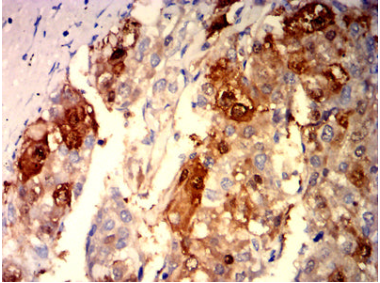

ARG1 Mouse Monoclonal antibody[6B4B1]

IHC    1/200-1/1000